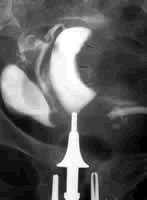

美国犹他大学医学中心Lee等的一项回顾性研究显示,对接受子宫及双侧输卵管切除术后的Ic期/1、3和4级子宫内膜腺癌患者实施辅助放疗(RT)可提高其生存率。

这项研究共纳入21249例按美国癌症分期联合委员会分期为Ia~c期,且无淋巴结转移的子宫内膜腺癌患者。研究者用Kaplan-Meier曲线绘制了这些患者的总体生存曲线,并对患者年龄进行矫正后,结合肿瘤的分期与分级,通过分层时序检验对结果进行了比较。

结果表明,在21249例患者中,有4080例患者(19.2%)接受了辅助RT,其余17169例患者(80.8%)未接受辅助RT。患者被确诊为子宫内膜癌时的平均年龄为63.2岁(14~99岁)。辅助RT可显著提高Ic期/1级患者(P<0.001)和Ic期/3、4级患者(P<0.001)的生存率。Cox相对风险回归分析显示,辅助RT与Ic期/1级(HR=0.44,P<0.001)和Ic期/3、4级(HR=0.72,P=0.009)患者相对生存率的改善之间存在统计学关联。在实施经腹全子宫加双侧输卵管切除术时,用手术淋巴结活检的方法对这些患者进行单独分析可得出相似的结论(Ic期/1级:HR=0.59,P=0.01;Ic期/3、4级:HR=0.73,P=0.02)。(JAMA 2006, 295:389)

研究提示:作为对早期子宫内膜癌患者实施辅助RT的最大规模人群分析报告表明,对Ic期(1、3和4级)患者实施辅助RT可显著提高患者的总体和相对生存率,且这种改善有统计学意义。今后尚需进行深入研究,确定可指导治疗决策的临床和生物学因素,并确定各亚组患者之间转归的差异。, 百拇医药